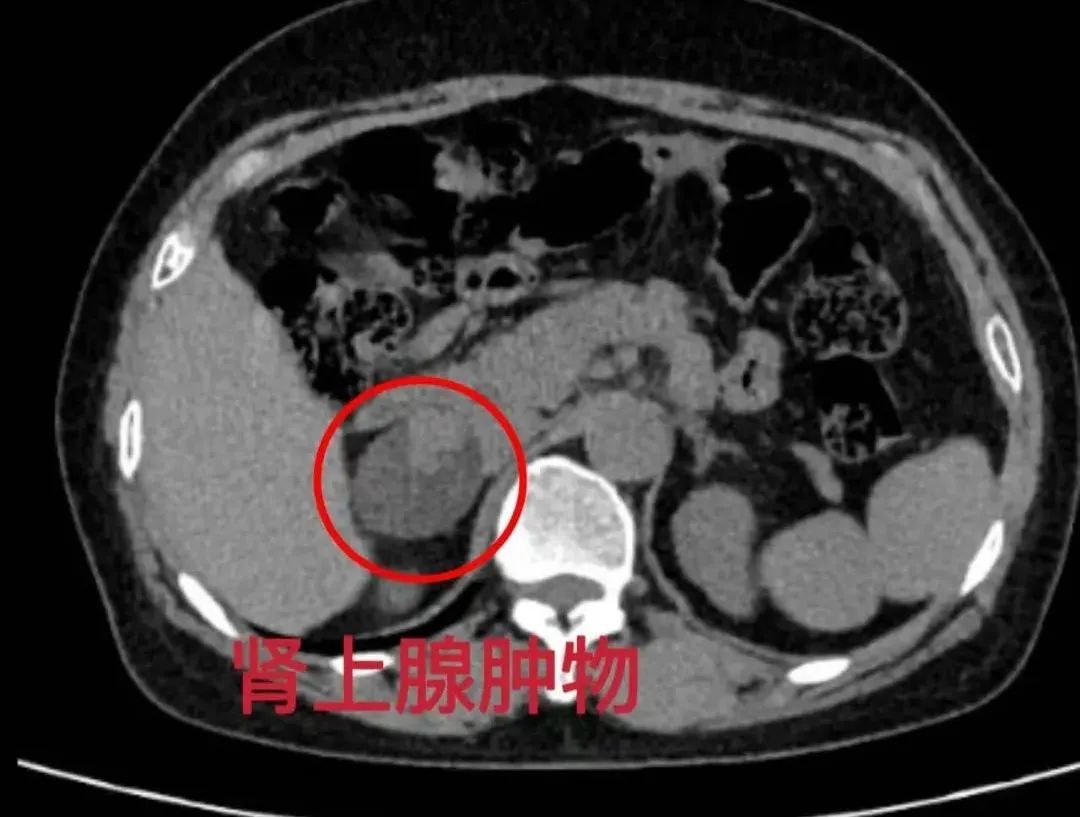

56岁常大姐平时身体硬朗,很少生病,在一次体检时意外发现肾上腺长了一个肿物,大小约4.1×3.3cm。这一突如其来的消息让常大姐感到震惊和不安,四处打听后来到寿光和信医院,泌尿外科梁化伟主任及其团队为期制定详细的手术方案,术后常大姐恢复良好,很快恢复了健康。

当肾上腺发生肿物,如果肿物没有任何功能,没有引起机体任何生理变化且大小<4cm,可无需处理,定期复查。但是肿物有功能并引发高血压、代谢紊乱、激素分泌异常等症状。需通过手术切除病变组织以恢复健康。手术切除是最有效的治疗手段。

腹腔镜下肾上腺肿物切除术,利用高清摄像头和精细器械精准切除病灶,体表仅有2-3个0.5-1cm的小切口,术后1-2天即可下床活动,住院时间缩短至3-5天,并发症发生率显著降低,具有创伤小、恢复快的优势。